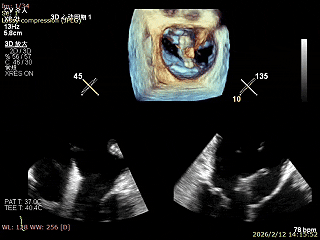

二尖瓣术前评估

复查TTE及TEE检查进一步评估二尖瓣情况。明确为AFMR,二尖瓣功能性反流,2区瓣叶运动,重度FMR(3+),肺静脉逆向血流;2区后叶长度13 mm,2区前叶长度20mm,AP径37mm,瓣口面积4.08cm²,房间隔高度4.5cm,瓣叶无钙化,二尖瓣瓣膜条件适合行TEER手术。

术前Bicom

二尖瓣2区功能性反流

二尖瓣三维视图

2区彩色血流